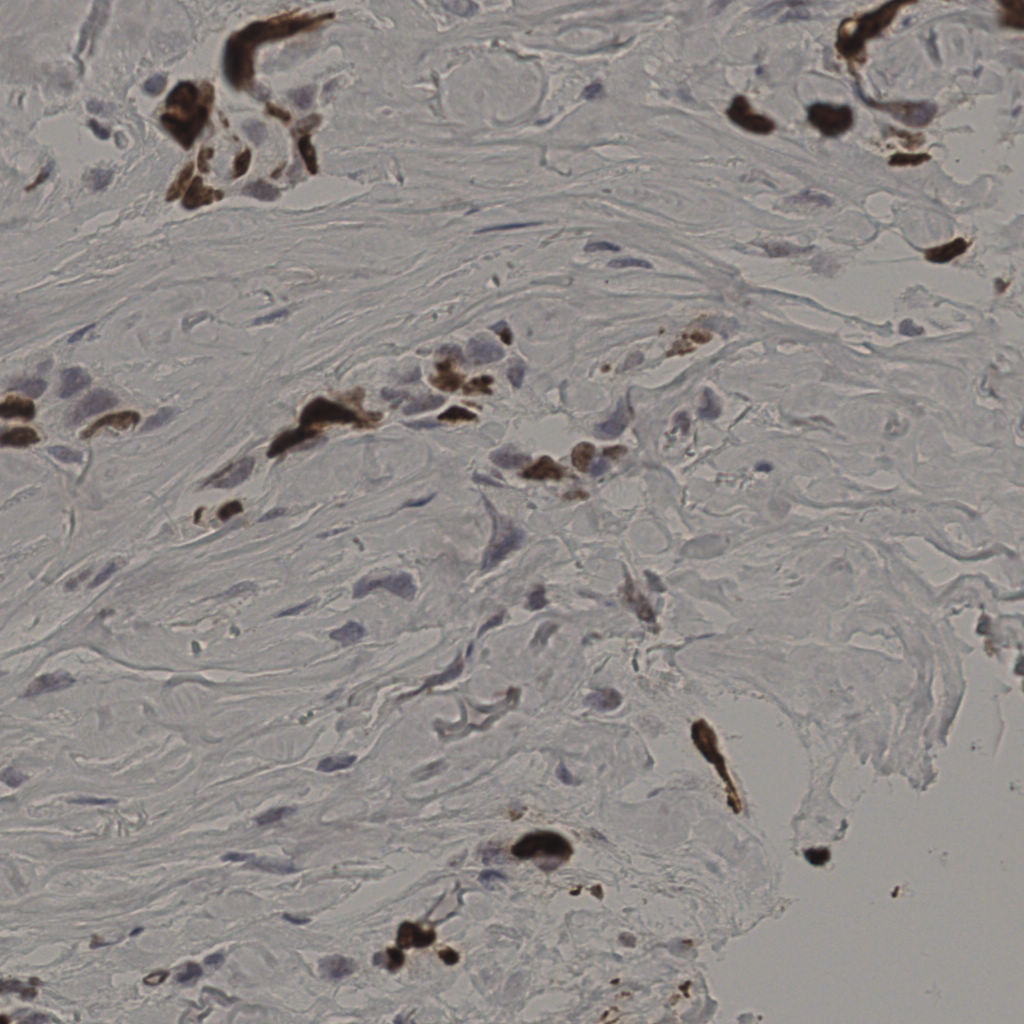

17.75%

Ki67 指数

阴 7986

阳 1723

切片统计

总切片

2640

有效

412

已标记

412

有效率

16%